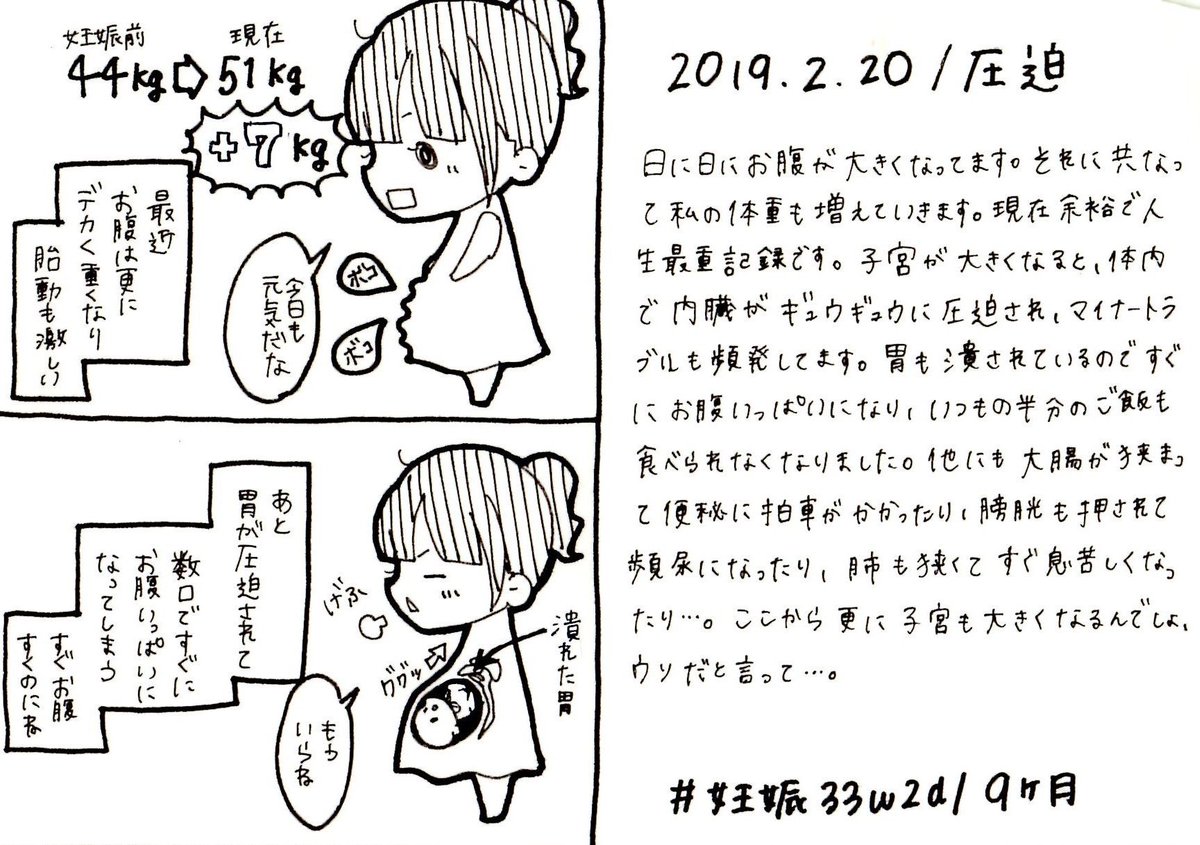

2019.2.20 妊娠中のマイナートラブルは地味にツラいですよね… エコーとお腹の写真載せます、閲覧注意! #育児漫画 #育児日記 #妊娠 #妊娠後期 #妊娠9ヶ月 #エコー #ママ垢さんと繋がりたい #オリジナル漫画 #絵描きさんと繫がりたい pic.twitter.com/vU5Xxj9IdW